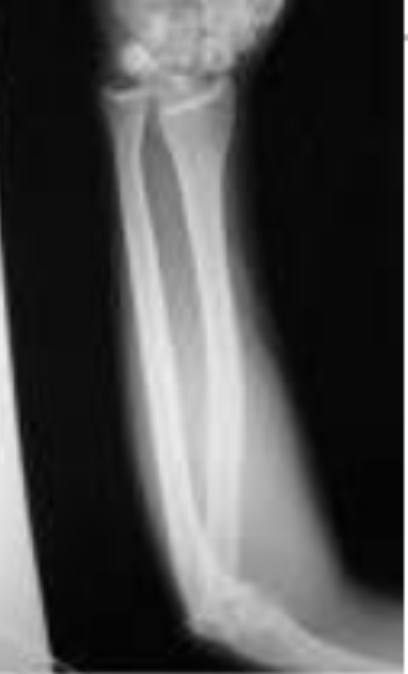

Tipo de fractura en esta rx

Fractura de bastonazo

Rotura aislada del cubito (por golpe directo)

Tratamiento

Placas de compresion dinamicas

Clavo endomedular para fx patologicas